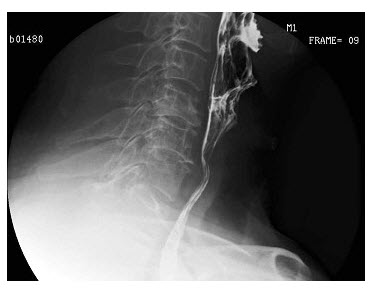

A.右侧肺气肿

143、多项选择题

男,64岁,进食梗阻感半月。体检:咽充血少许滤泡,结合图像,最可能的诊断为()

A.会厌征

B.颈椎退变

C.食管癌

D.食管型颈椎病

E.以上都不是